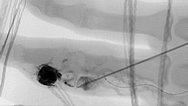

Fluoroskopische Darstellung der Punktionsnadel bei Beginn der direkten perkutanen Embolisationstherapie am Finger mit einem Flüssigembolisat (EVOH). Zusätzlich sichtbar der nicht ganz bis zum Nidus vorgeschobene Mikrokatheter.